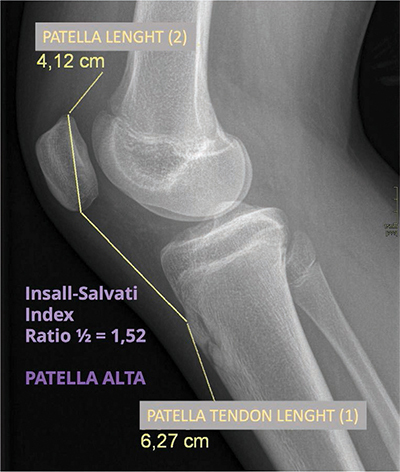

教学要点:股骨前脂肪垫撞击综合征是膝关节脂肪垫撞击的一种,可通过超声波检查进行评估。

Teaching point: Prefemoral fat pad impingement syndrome is one of the fat pad impingements of the knee and can be assessed with ultrasonography.